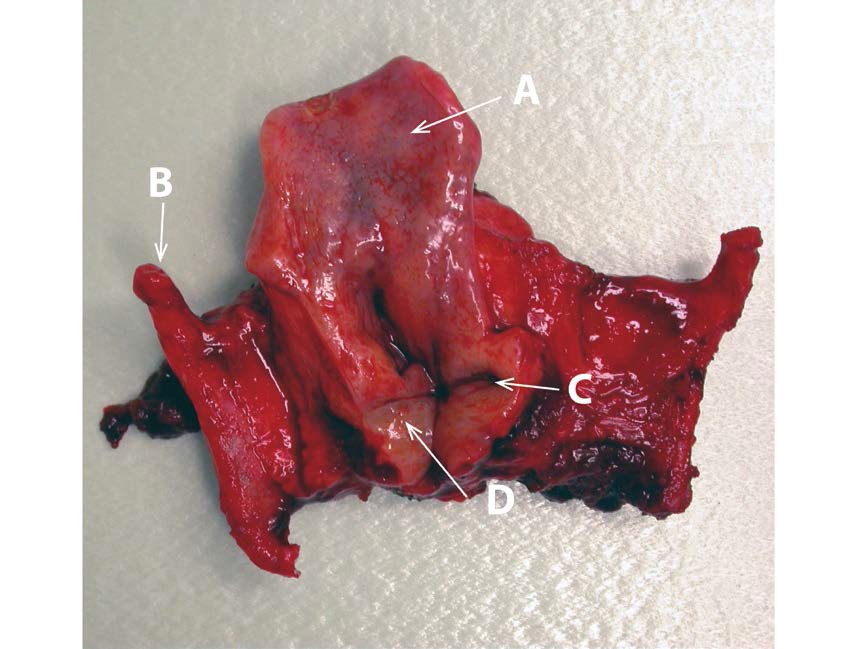

a. Name the structure indicated by the Arrow labelled ‘A’? (2 marks)

Answer: Epiglottis

b. The infective process causing gross swelling of the structure indicated by the Arrow labelled ‘A’ is now rare due to childhood immunization. What is the classic causative organism that has been targeted by immunization? (2 marks)

Answer: Haemophilus Influenzae Type B

c. What movement does the structure (transected at its posterior end) indicated by the Arrow labelled ‘D’ perform during the laryngeal phase of swallow? (2 marks)

Answer: Adduction

d. The movement, identified in Part ‘c’ of this question, occurs due to innervation by which nerve?

Answer: Left recurrent laryngeal nerve